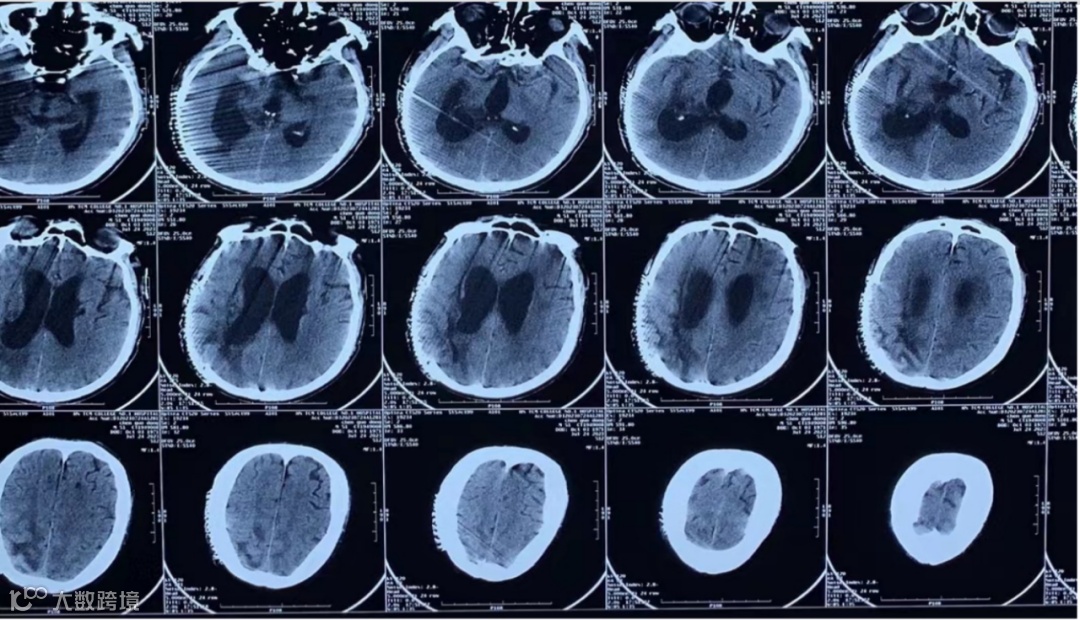

既往史:8月前(2022-12-09)因“右侧基底节区脑出血破入脑室”,于当地医院性“去骨瓣减压术”(图3),术后四肢瘫痪、植物状态。1月余前(2023-06-07)于“北京XX医院”行“脑刺激器”植入术。

图3. 8月前外院头颅CT检查

图4. 入院前外院复查头颅CT